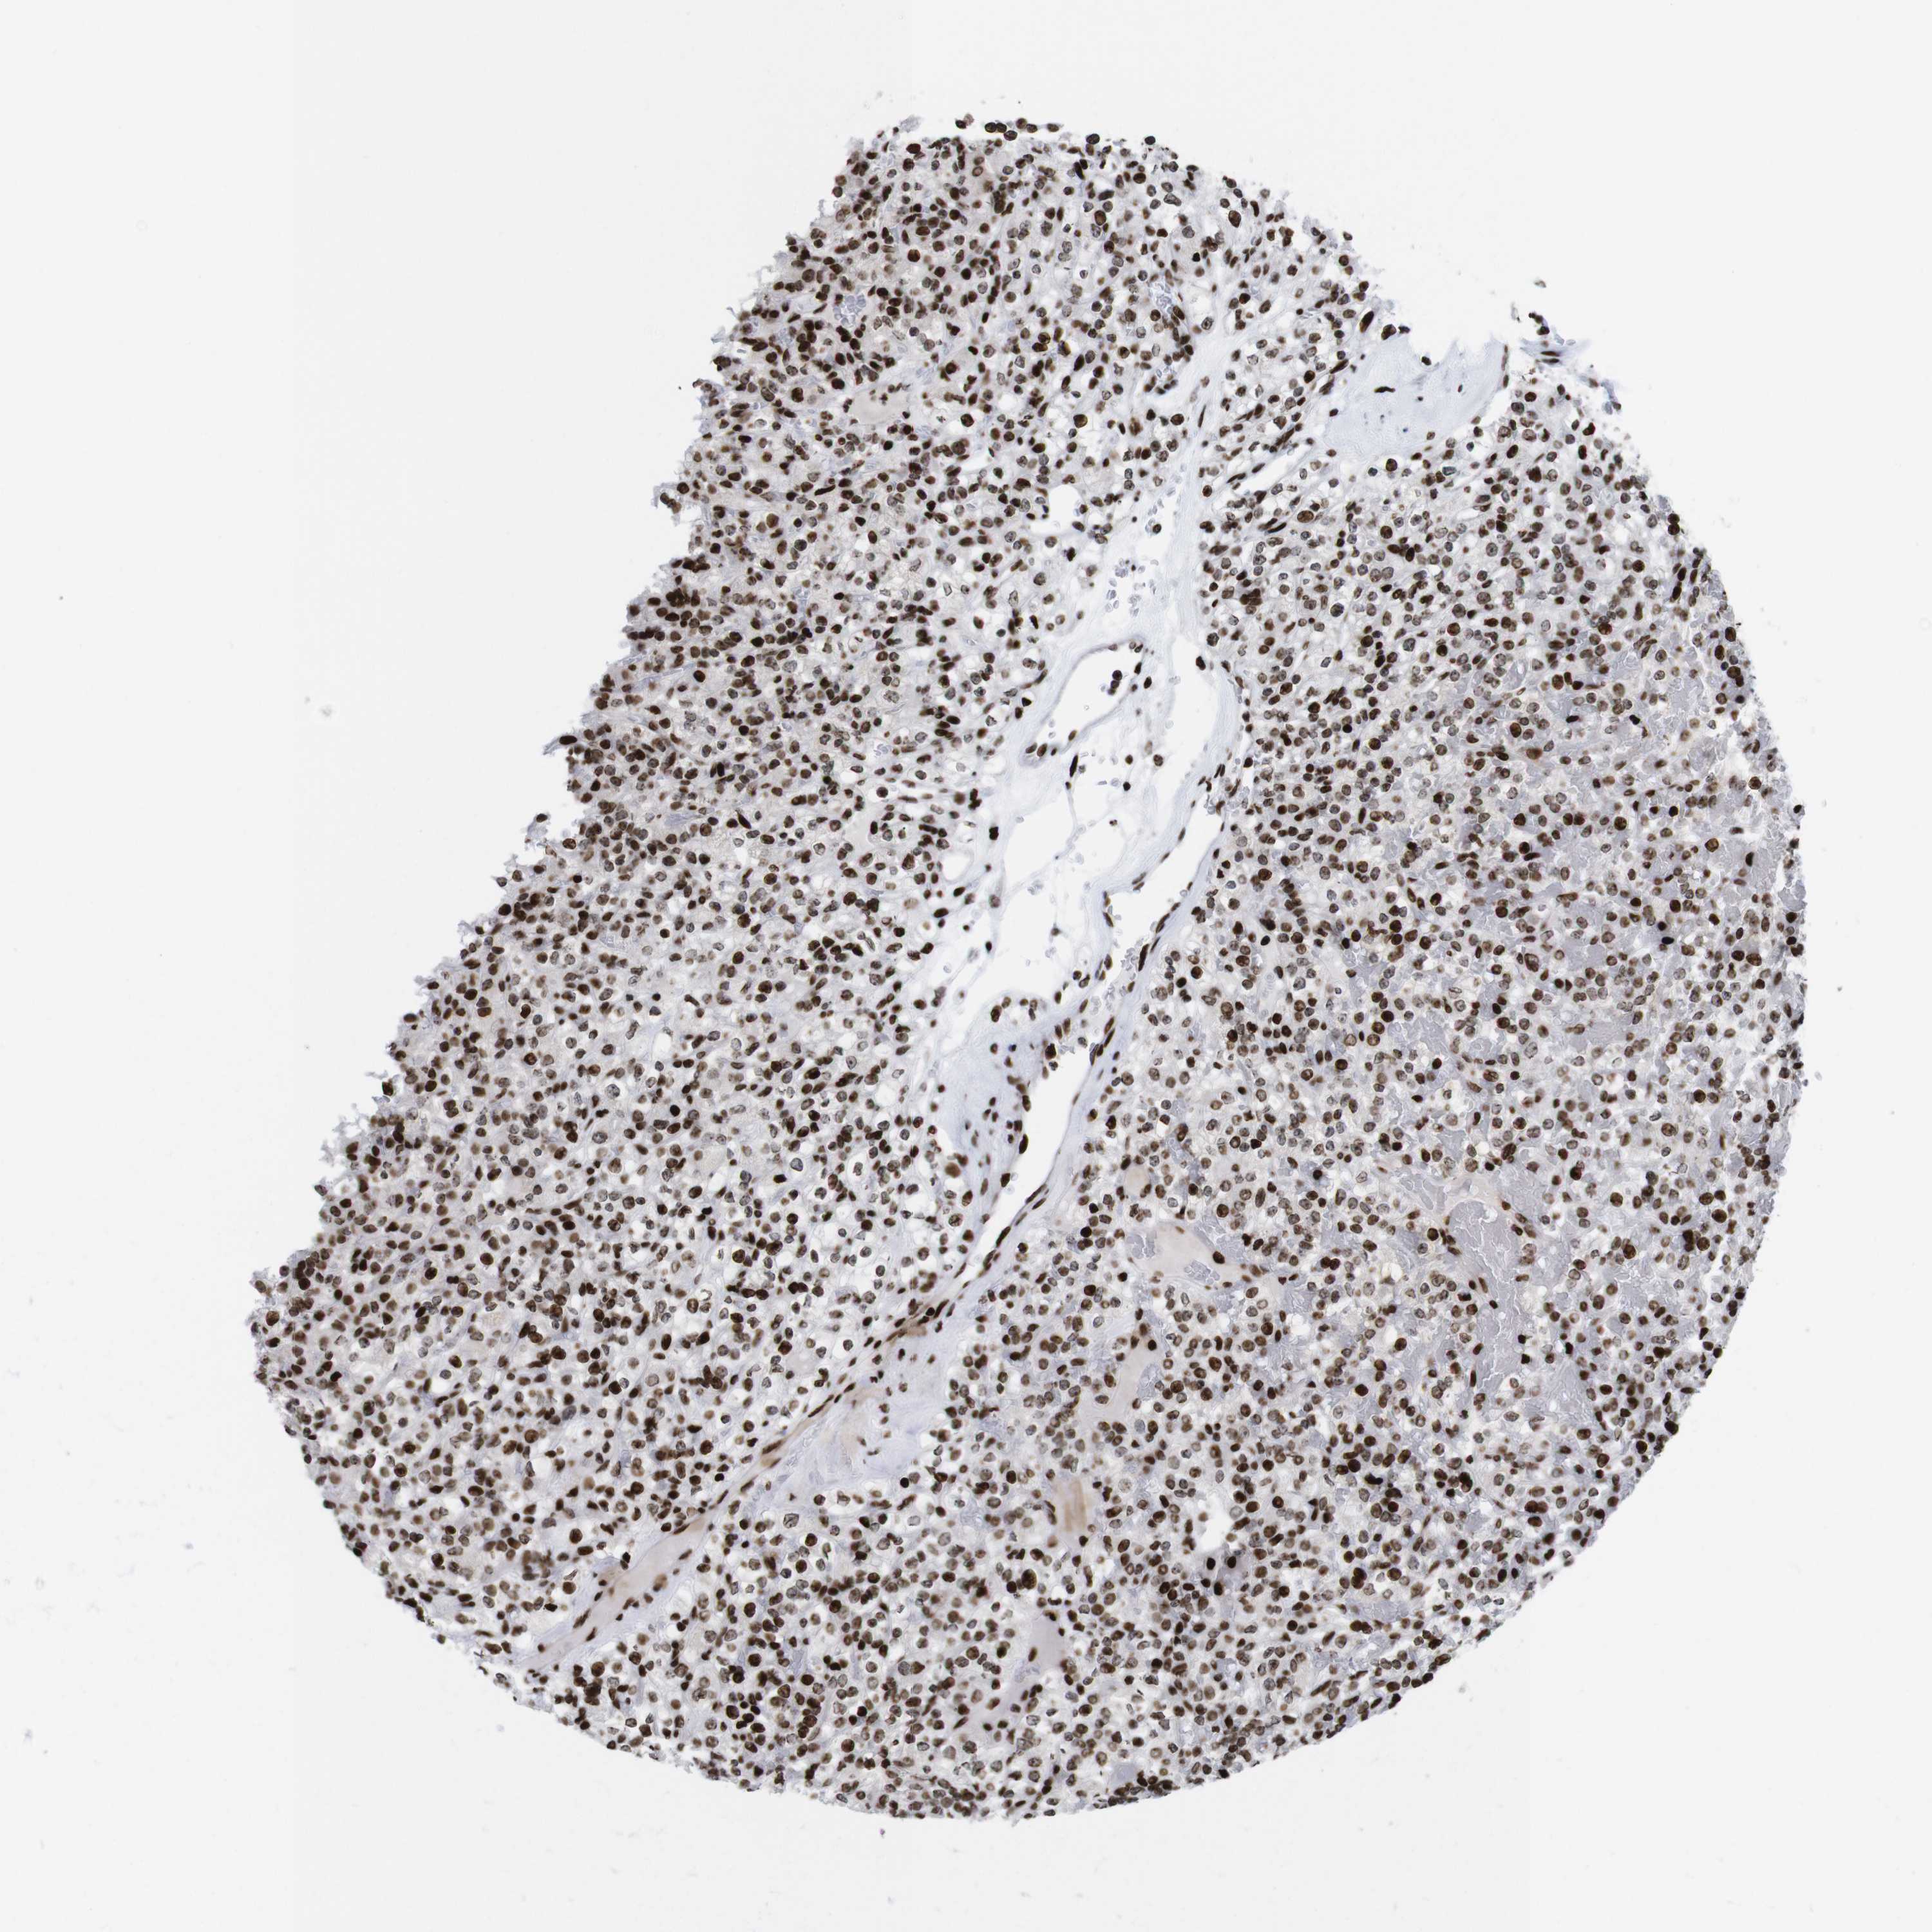

KIDNEY RENAL CLEAR CELL CARCINOMA (VALIDATION) - Interactive survival scatter ploti

The Survival Scatter plot shows the clinical status (i.e. dead or alive) for all individuals in the patient cohort, based on the same data that underlies the corresponding Kaplan-Meier plots. Patients that are alive at last time for follow-up are shown in blue and patients who have died during the study are shown in red.

The x-axis shows the expression levels (FPKM) of the investigated gene in the tumor tissue at the time of diagnosis. The y-axis shows the follow-up time after diagnosis (years). Both axes are complimented with kernel density curves demonstrating the data density over the axes. The top density plot shows the expression levels (FPKM) distribution among dead (red) and alive patients (blue). The right density plot shows the data density of the survived years of dead patients with high and low expression levels respectively, stratified using the cutoff indicated by the vertical dashed line through the Survival Scatter plot. This cutoff is automatically defined based on the FPKM cutoff that minimizes the p-score. The cutoff can be changed by dragging the vertical line or by entering a cutoff value in the square labeled "Current cut-off".

Under the Survival Scatter plot the p-score landscape (black curve; left axis) is shown together with dead median separation (red curve; right axis). Dead median separation is the difference in median mRNA expression between patients who have died with high and low expression, respectively. It is calculated as follows: median FPKM expression of dead patients with high expression - median FPKM expression of dead patients with low expression. This is intended to aid the user in visually exploring custom cutoffs and the associated p-scores and dead median separation.

Individual patient data is displayed and can be filtered by clicking on one or more of the category buttons on the top of the page. Categories describing expression level and patient information include: high, low, alive, dead, female, male and tumor stages. The scale of the x-axis can be toggled between linear and log-scale by clicking on the "x log" button. Mouse-over function shows TCGA ID, patient information and mRNA expression (FPKM) for each patient.

& Survival analysisi

Kaplan-Meier plots summarize results from analysis of correlation between mRNA expression level and patient survival. Patients were divided based on level of expression into one of the two groups "low" (under cut off) or "high" (over cut off). X-axis shows time for survival (years) and y-axis shows the probability of survival, where 1.0 corresponds to 100 percent.

H1-4 is not prognostic in Kidney Renal Clear Cell Carcinoma (validation)